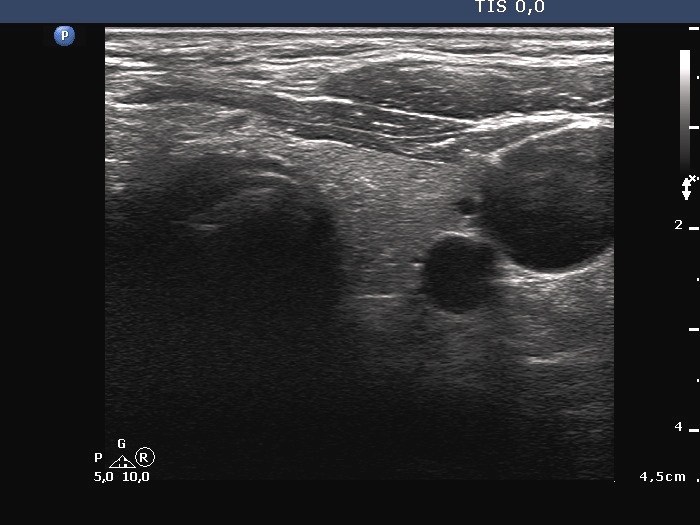

Ultrasonography. The thyroid was echonormal. A large hypoechoic nodule occupied almost the entire right lobe. The nodule showed various intranodular echogenic figures, including microcalcifications, macrocalcification and non-specific figures. The borders were indistinctive. The lesion was suspicious spreading extrathyroidal.